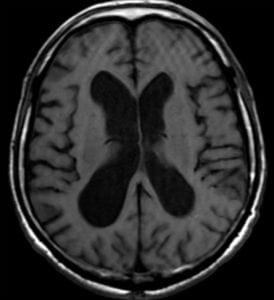

- CT/MRI

- Widening of the cortical sulci and enlargement of the lateral ventricles

- Hippocampal and high parietal atrophy